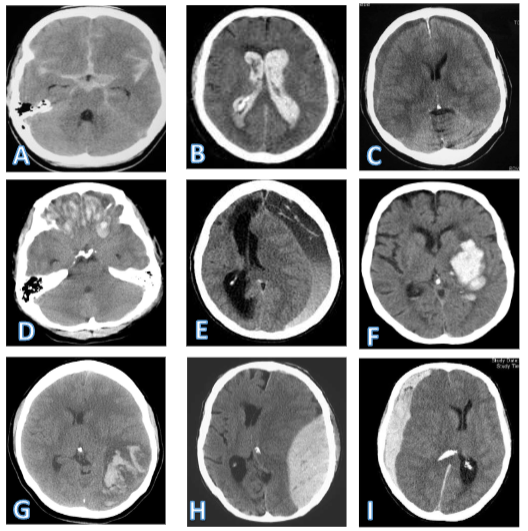

Sæt billeder sammen med korrekt beskrivelse: 1. Epiduralt hæmatom 2. Akut subduralt hæmatom 3. Kronisk subduralt hæmatom 4. Subaraknoidalblødning 5. Intraventrikulær blødning 6. Intracerebralt hæmatom 7. Cerebral kontusion 8. Hæmorrhagisk infarkt (1 genganger - max 1 fejl)

A: Subaraknoidalblødning

B: Intraventrikulær blødning

C: Kronisk SDH (bilateralt)

D: Cerebral kontusion

E: Kronisk SDH

F: Intracerebralt hæmatom

G: Hæmorrhagisk blødning

H: Epiduralt hæmatom

I: Akut SDH